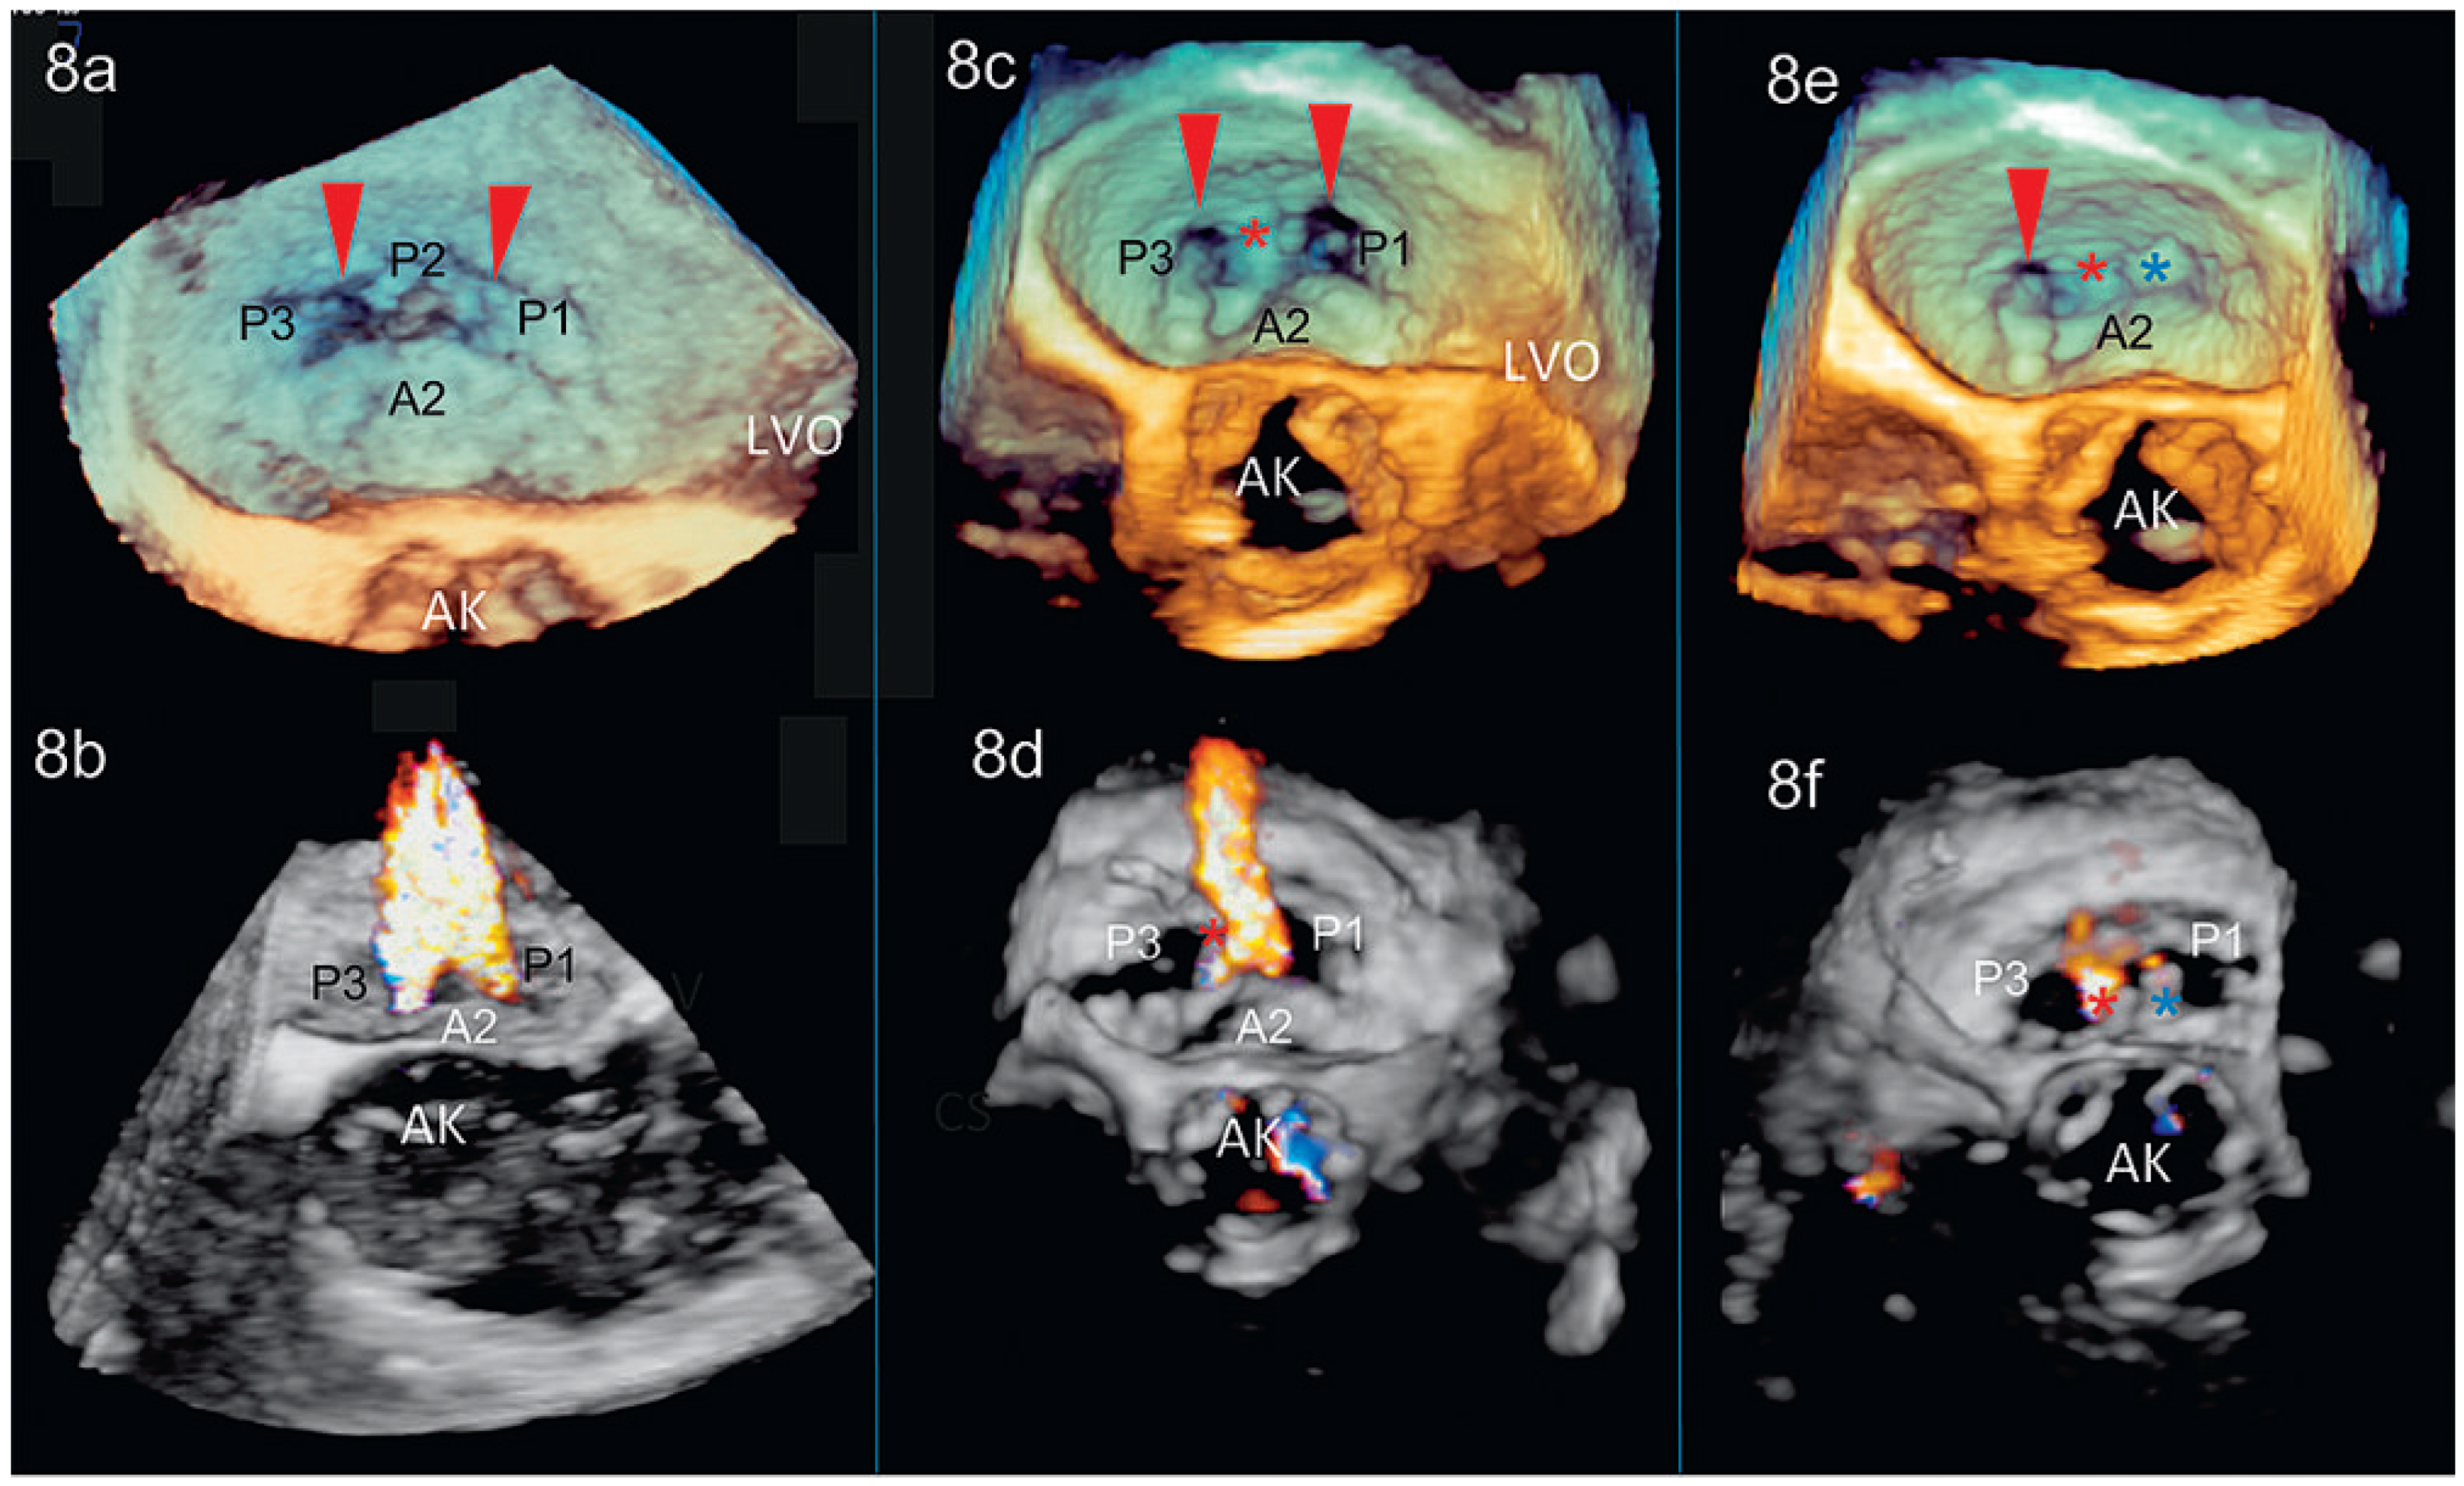

3D-TEE